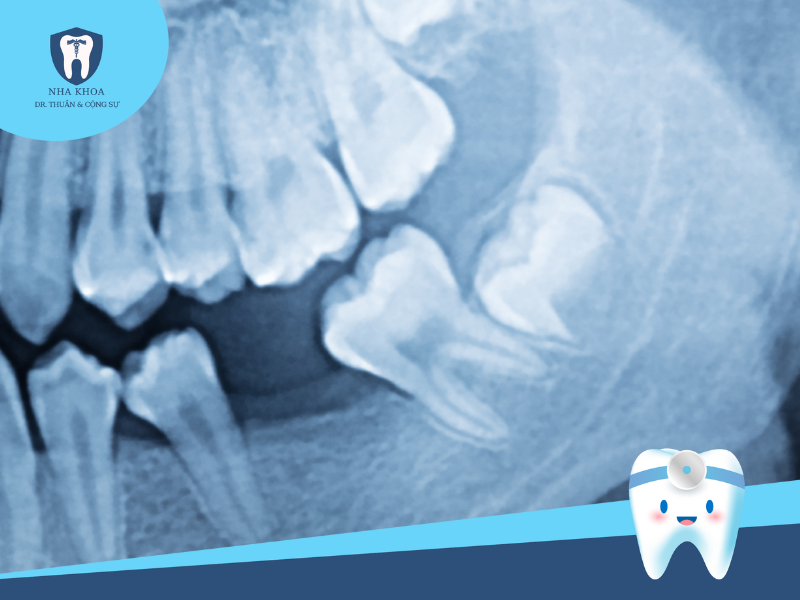

Đây là bước đầu tiên nhưng cũng rất quan trọng trong quy trình nhổ răng khôn. Theo đó, nha sĩ sẽ thực hiện các biện pháp thăm khám để đánh giá tình trạng tổng quát, cũng như khám kĩ để xem xét tình trạng, vị trí, mức độ tổn thương... của răng. Sau đó, bác sĩ sẽ cho bệnh nhân chụp phim X-quang hàm răng để đánh giá hình ảnh chính xác về tư thế và vị trí răng khôn mọc, giúp nha sĩ nắm rõ và xây dựng kế hoạch nhổ răng phù hợp và ít sang chấn cho người bệnh.

Răng khôn mọc lệch khi nhìn qua X-quang